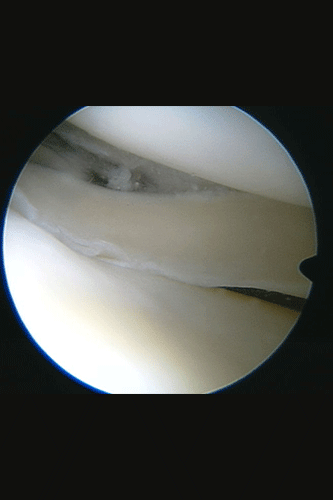

Bei einer Gelenksspiegelung werden über ca. 1 cm lange Hautschnitte eine Kamera und Arbeitsinstrumente in das betroffene Gelenk eingebracht. Das erhaltene Bild wird auf einen Fernsehmonitor übertragen. Der Chirurg muss also das Gelenk für die Operation nicht mit dem chirurgischen Skalpell eröffnen, um den Eingriff vorzunehmen.

Die Mehrzahl aller gelenkserhaltenden Kniegelenksoperationen und auch viele Operationen an anderen Gelenken ist so durchzuführen. Erst durch diese schonende Operationsmethode ist es möglich geworden, Eingriffe am Meniskus, Knorpel und an den Kreuzbändern ambulant vorzunehmen.